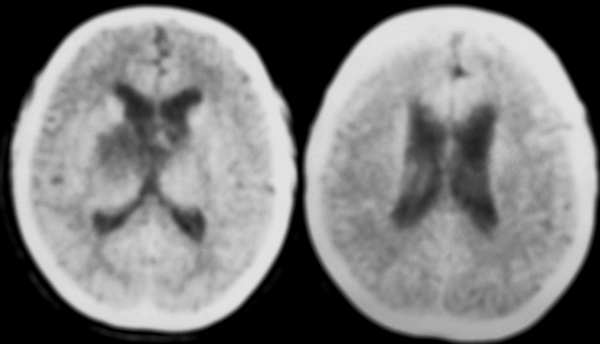

ct扫描显示:中线部位鞍上可见一圆形低密度病变,边缘清晰,密度尚均匀,ct值与脑脊液相仿,囊内左后是点状钙化影,病变向下葡行生长至脚间池,脑干受压变形;脑室系统未见明显异常.

鞍上囊状占位,囊壁结节钙化,囊内密度均匀,似乎内有脂类密度。诊断颅咽管瘤。

鞍上区的囊性占位,ct值略高于脑脊液密度,左后方有斑片状钙化,侧脑室无明显扩张增大;考虑:表皮样囊肿。期待结果。

ct表现:鞍上区圆形、类圆形、不规则肿块,密度随成分差异较大,亦完全囊变和部分囊变多见,一般呈脑脊液样密度,也可因含较多胆固醇呈很低密度,含钙质、蛋白质呈稍高密度,也可完全实性。钙化率高,可沿边缘呈壳状,实质部分可呈点状、斑片状、不规则团块状。